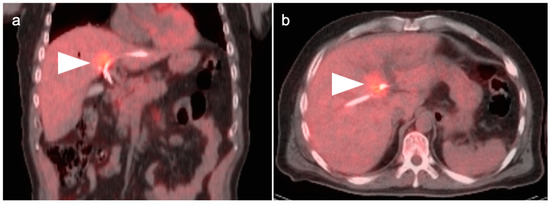

4. Hepatocellular Carcinoma